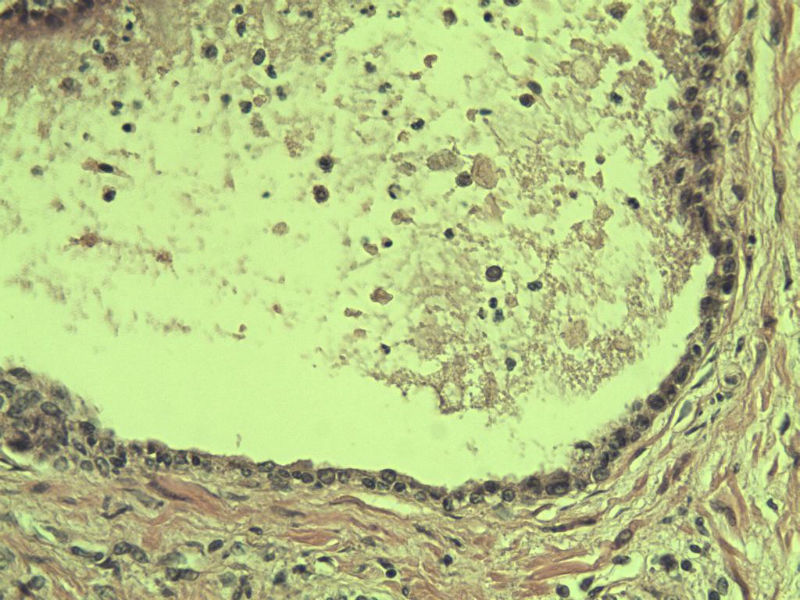

男 75岁 因排尿困难半年行前列腺切除术,体积 4 × 3 × 2.5 cm3,切面灰白,实性,质韧。请各位老师看看 有问题没? 谢谢了!

高级别上皮内瘤变,建议免疫组化:P63、34BE12、P504S

前列腺增生症伴鳞化

良性前列腺增生伴尿路上皮化生

呈巢上皮为尿道周围前列腺组织正常现象。尿路上皮-前列腺腺体过度。

良性。

前列腺增生伴尿路上皮鳞化及Brown巢形成,未见恶性。